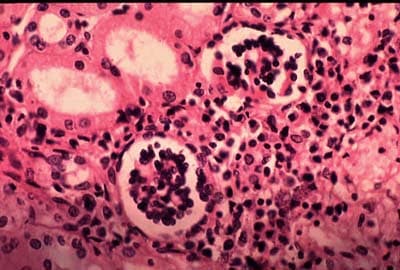

Visceral leishmaniasis (VL), also known as kala-azar (Hindi: kālā āzār, "black sickness") or "black fever", is the most severe form of leishmaniasis and, without proper diagnosis and treatment, is associated with high fatality. Leishmaniasis is a disease caused by protozoan parasites of the genus Leishmania. The parasite migrates to the internal organs such as the liver, spleen (hence "visceral"), and bone marrow, and, if left untreated, will almost always result in the death of the host. Signs and symptoms include fever, weight loss, fatigue, anemia, and substantial swelling of the liver and spleen. Of particular concern, according to the World Health Organization (WHO), is the emerging problem of HIV/VL co-infection. VL is the second-largest parasitic killer in the world (after malaria), responsible for an estimated 20,000 to 30,000 deaths each year worldwide. Upendranath Brahmachari synthesised urea stibamine (carbostibamide) in 1922 and determined that it was an effective substitute for the other antimony-containing compounds in the treatment of VL caused by Leishmania donovani. When people develop visceral leishmaniasis, the most typical symptoms are fever and the enlargement of the spleen, with enlargement of the liver sometimes being seen as well. The blackening of the skin that gave the disease its common name in India does not appear in most strains of the disease, and the other symptoms are very easy to mistake for those of malaria. Misdiagnosis is dangerous, as without proper treatment the mortality rate for kala-azar is close to 100%. L. donovani itself is not usually the direct cause of death in people with kala-azar, however. Pneumonia, tuberculosis, and dysentery are omnipresent in the immuno-depressed regions where leishmaniasis thrives, and, as with AIDS, it is these opportunistic infections that are more likely to kill, flaring up in a host whose immune system has been weakened by the L. donovani infection.